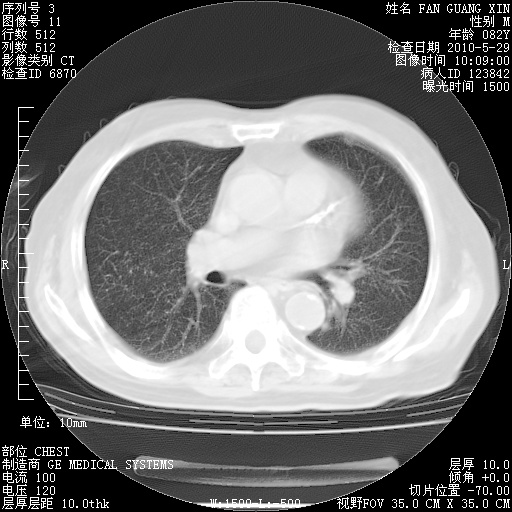

再治疗10天后的肺部CT

从白细胞总数和中性比例看好像合并感染。肺部纹理好像比上次多,支气管炎?其他感染?

阅读此次胸部CT,肺间质渗出性改变较入院时有吸收。目前从体温、白细胞、中性分叶明显增高,肯定存在细菌感染(发生医院感染哦,若无消化道及泌尿系统等感染的依据,肺部感染可能大)。若你院头孢哌酮舒巴坦钠耐药率较高,同意你的方案,若48小时体温仍高,可考虑使用碳青霉稀类抗菌药物,同时可予超声雾化、注意滴数时加大液体量。白蛋白33.30g/L较低哦,需加强营养等支持治疗。